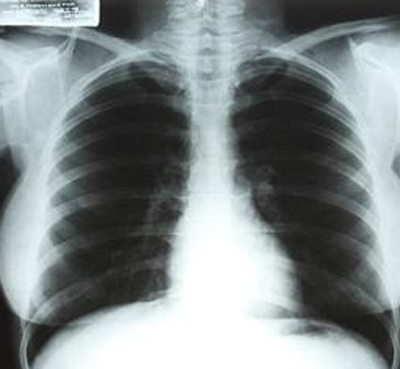

中新網4月14日電 據臺灣“今日新聞”消息,好萊塢性感女星瑪麗蓮.夢露生前的一張X光片即將舉行拍賣。

報道稱,這張X光片是1954年時,夢露在洛杉磯Cedars of Lebanon醫院里拍下的。據悉,此張X光片可望以38萬4000美元左右的售價拍賣出去。